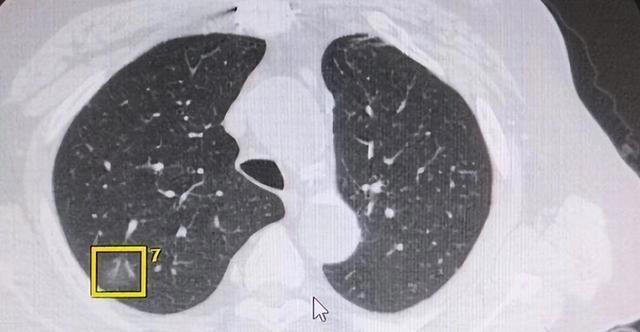

第二个:报告出现"毛刺征"、"分叶征"或"胸膜牵拉凹陷"

这几个词放在一起,专业上称为"形态学恶性征象",说的是结节长得不正常。良性结节通常边缘光滑、整齐,而恶性结节往往"不守规矩",边界不清、形状怪异。

毛刺征是指结节边缘向周围组织伸出细小的条索状影,这是肿瘤细胞向外浸润蔓延的一种影像学表现,不是普通炎症能做到的。

分叶征指结节的轮廓呈波浪状或分叶状,原因在于肿瘤在不同方向上的生长速度不一致,导致形状凹凸不平。

胸膜牵拉凹陷则说明结节和胸膜之间产生了牵连,局部胸膜被"拉"出了一个小坑,这通常意味着病灶对周围组织已经产生了一定程度的影响。

这三种征象单独出现时,恶性可能性已经升高;两种或三种同时出现,风险叠加明显。国内相关研究数据显示,同时具备毛刺征和分叶征的实性结节,恶性概率可超过60%。

不过有一点需要说清楚,CT征象只是影像学参考,恶性与否的最终定性,依然要靠病理结果,不能凭报告上几个词就给自己扣帽子,但也绝不能置之不理。